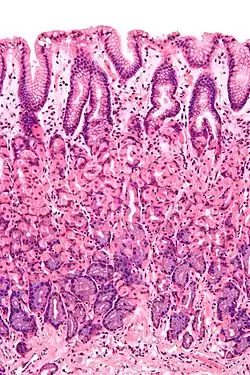

Mucosa

Mucosa ou membrana mucosa é um tipo de tecido epitelial de revestimento interno das cavidades do corpo que têm contato com o meio externo.[1]

Corte histológico do antro pilórico, onde se observa a mucosa do estômago | |

"O epitélio do intestino delgado, por exemplo, é constituído por uma camada simples de células cilíndricas, que lhe permitem executar sua principal função: absorver o alimento. Por isso, essas células possuem dobras - as microvilosidades ou microvilos -, que aumentam a área de absorção do alimento. Nesse caso, a proteção do organismo é feita pelo muco, substância viscosa formada por glicoproteínas e produzida por células especiais - as células caliciformes -, encontradas em vários órgãos."

Mucosa é o nome dado ao conjunto formado por epitélio mais tecido conjuntivo que reveste as cavidades úmidas do corpo, em contraste com a pele onde a superfície é seca. Portanto, recobre locais como a boca, intestino, bexiga, etc. Seu tecido conjuntivo é denominado lâmina própria ou córion.